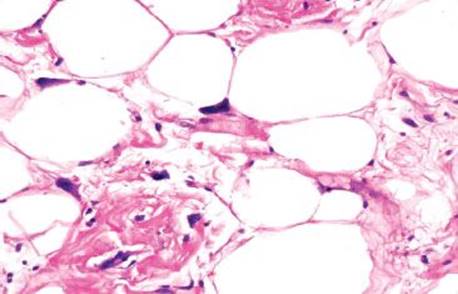

MUCIPHAGES

Azzopardi described muciphages as mucoprotein-containing macrophages in the rectum in 1966.124 The incidence was as high as 50% of rectal biopsies and no correlation with sex, age, or underlying disease was found. Academic interest in muciphages was likely borne out of the 1960s burgeoning understanding of Whipple disease, and a concern that muciphages represented Whipple disease involving the rectum. Today we know muciphages are extraordinarily common with essentially no relation to Whipple disease. A more recent study describes the muciphages as superficially located in the lamina propria and found that up to 19% present as nodules or polyps.2 These experts found a backdrop of increased chronic inflammation and mild fibrosis and suggest muciphages represent nonspecific, resolving injury. Their mucin presumably originates from “clean up” of epithelial damage or turnover (Figs. 4.263–4.269). Detailed studies show the mucin contains neutral, weakly acidic, or strongly acidic mucin with predominantly sialomucin but also a smaller component of sulfated mucin.2 The clinical importance of muciphages is simply to be aware of their benign and nonspecific nature. AFB and GMS special stains are not required upon identification because muciphages are not granulomata and have no association with infections.

Figure 4.265 Muciphages. Under oil magnification, the bland nuclear features are seen. Dislodged muciphages can occasionally raise concerns for signet ring cell carcinoma. Helpful clues to the diagnosis of benign muciphages include the bland cytology and lack of background dysplasia and desmoplasia. In difficult cases, CD68 will confirm their histiocytic origin. Muciphages are cytokeratin nonreactive.

To those unfamiliar with muciphages, they can appear alarming at first. An interesting consultation case featured a prostate biopsy accompanied by bystander rectal tissue with prominent muciphages. The muciphages had become dislodged and “squished” and raised concerns for signet ring cell carcinoma. Helpful diagnostic clues include that the muciphages display bland cytologic features, immunolabel with the histiocytic marker CD68, and are cytokeratin nonreactive.